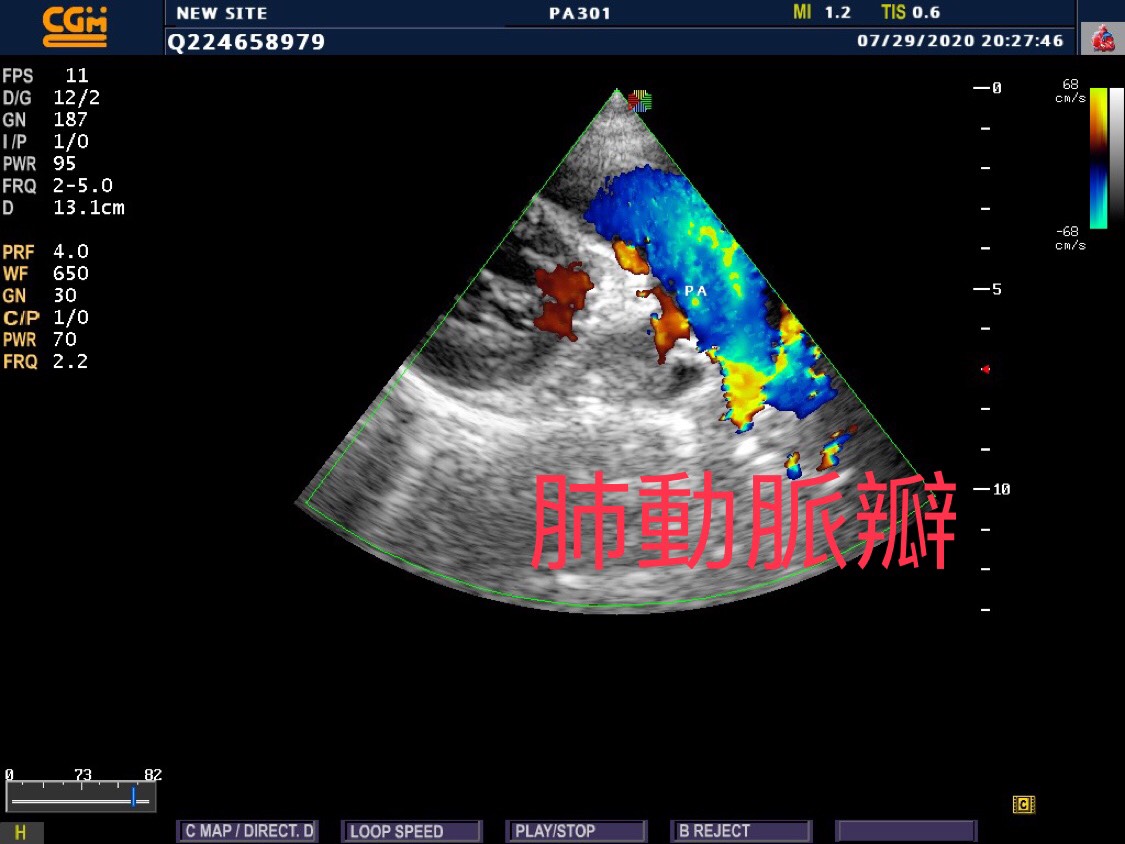

心臟超音波